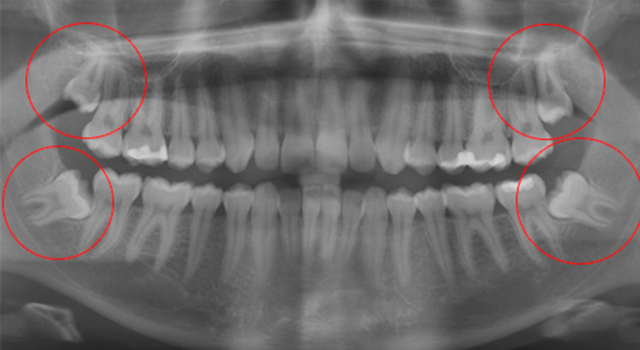

Проблемы с «восьмерками» начинаются еще тогда, когда они не успели вырасти: на этапе их прорезывания. Любое отклонение зуба от вертикальной оси является патологией, которая называется дистопией. В зависимости от направления, в котором отклоняется зуб мудрости, выделяют несколько ее типов:

так растут зубы мудрости при дистопии

В процессе роста зуб мудрости может зацепиться за соседний моляр и развернуться под десной. В таком случае есть вероятность, что наружу он уже не покажетсяЕсли притесненному зубу повезет, он может все-так прорезаться, но частично. Или криво — тогда его называют дистопированным.Красными стрелками на рентгене обозначены дистопированные «восьмерки» у пациента